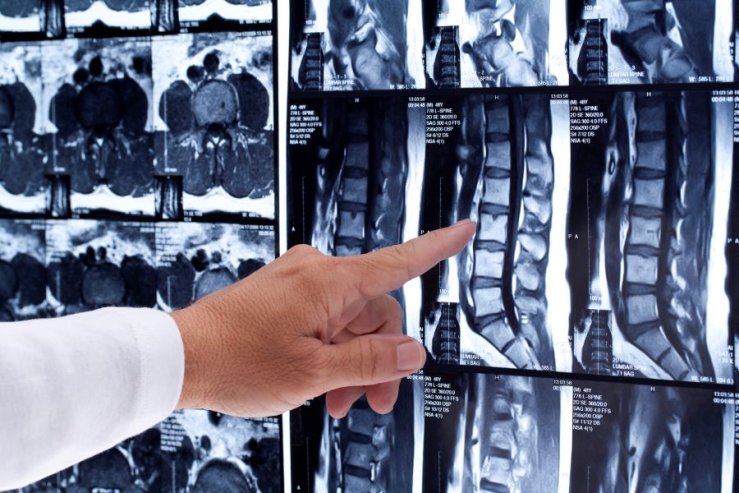

Відділення спеціалізується на лікуванні захворювань і травм хребта, спинного мозку та периферичних нервів — від міжхребцевих гриж і стенозів до пухлин та складних наслідків травм. Тут пацієнтам повертають рухливість, силу та якість життя.

Хірурги застосовують мікрохірургічні та малоінвазивні технології, зокрема:

- транспедикулярні системи стабілізації (“DIAM”, “Medtronic”, “Stryker”),які дозволяють вставати вже через кілька днів після операції;

- пункційну вертебропластику для зміцнення тіл хребців при остеопорозі чи пухлинах;

- електростимуляцію периферичних нервів, що пришвидшує відновлення рухів і чутливості.